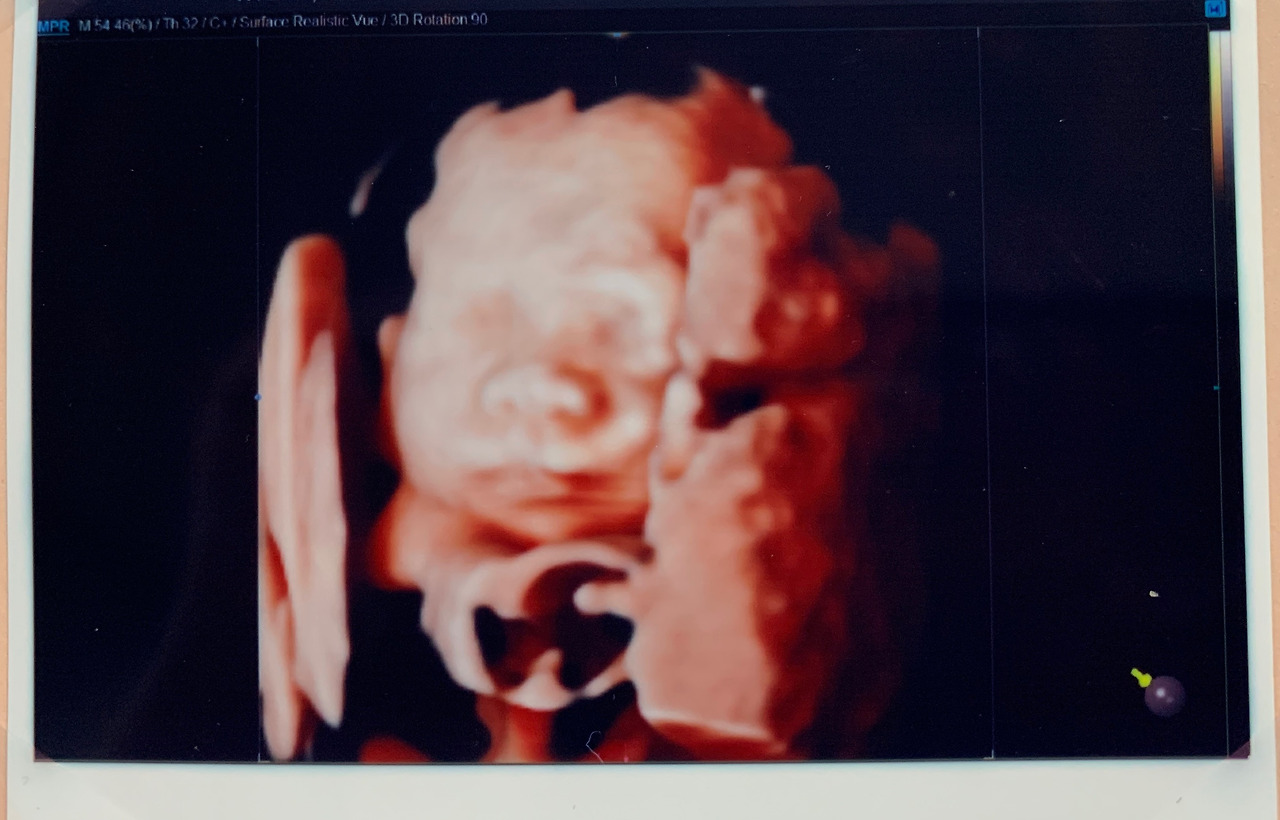

나날이 아빠 붕어빵이 되어가던 시절의 초음파 사진

그 날은 밤늦게까지 잠들지 못했다. 잠들지 못하는 그 시간 내내, 나는 반짝이의 초음파 동영상과 사진들을 봤다. 배를 어루만지고, 좋아하는 음악을 들으며 마음을 추슬렀다. 그리고 신기하게도 바닥으로 가라앉기만 하던 마음이 조금씩 위로 떠올랐다. 그래, 할 수 있어. 이렇게 작은 애도 크게 심장을 쿵쾅거리며 내 안에서 살려고 애를 쓰는 걸. 나도 할 수 있어. 그 밤은 아직도 내게 잊을 수 없는 순간으로 남아있다.

그냥 한없이 초음파 사진과 동영상을 본다.

아마 지금도 내 뱃속에서 작은 손발을 꼼지락거릴, 우리 반짝이.